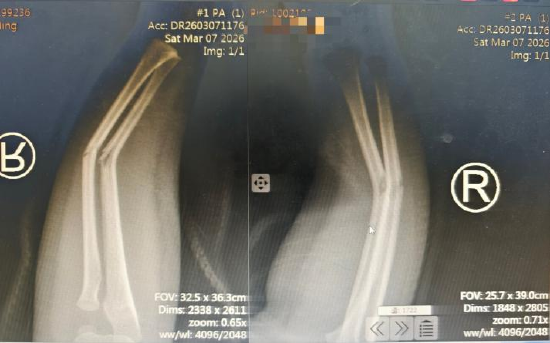

这名小患者是在玩耍时不小心摔伤的,右前臂当即出现肿痛、变形,家人赶紧把他送到了医院。接诊的杜龙龙主治医师仔细检查后,确诊为右前臂桡尺骨双骨折,而且断端错位很明显。考虑到孩子正处于生长发育的关键阶段,杜医生解释,如果这种骨折处理不好,很可能会影响到他未来的骨骼发育和手臂功能。

在董博主任医师、周健副主任医师的精准指导下,杜龙龙主治医师凭借娴熟的技术,在X光透视辅助下,精准把控力度与方向,轻柔而稳健地完成牵引、复位等一系列操作。整个过程创伤为零,痛苦降至最低。复位后影像复查显示:骨折端对位对线良好,畸形消失,复位成功!